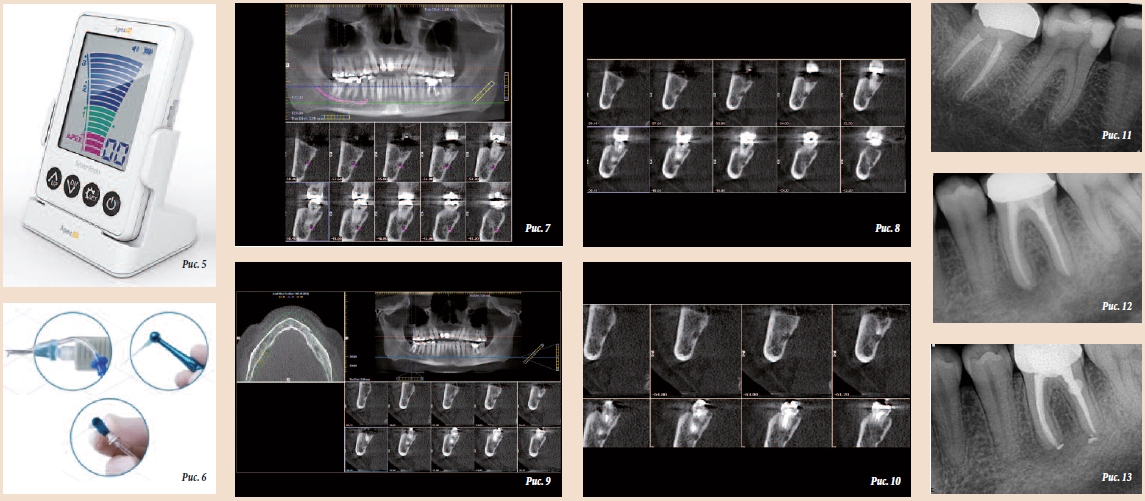

Носитель удалось захватить и извлечь из канала (рис. 4). После распломбирования каналов и точного определения рабочей длины с помощью апекслокатора Apex ID (Axis, Sybron-Endo; рис. 5) каналы были обработаны на рабочую длину с помощью инструментов SM в режиме TF Adaptive; чтобы уменьшить воспаление за счет охлаждения корней, использовали ирригационную систему EndoVac (Sybron-Endo; рис. 6) с холодным физраствором. Все каналы промывали как минимум 20 мин. Целью являлось быстрое снятие воспаления в нижнечелюстном канале, отличающемся слабой иннервацией. Уменьшение воспаления внутри нерва и вокруг него занимает некоторое время, но нужно было добиться этого как можно быстрее. Каналы оставили незаполненными, полость доступа закрыли ватным тампоном и загерметизировали сверху.

Немедленно сделали компьютерную томографию – КТ (i-CAT, Imaging Sciences International). Томограмма неожиданно показала, что нижнечелюстные каналы слева и справа расположены несимметрично и что пораженный канал контактировал с верхушкой корня второго моляра, который и был подвергнут эндодонтическому лечению (рис. 7).

Пациенту назначили противовоспалительные препараты и продолжили наблюдение. Через несколько дней подвижность губы восстановилась, однако ее чувствительность все еще была несколько снижена. Спустя 30 дней повторно провели КТ (рис. 8), чтобы оценить степень воспаления нерва; в течение всего этого времени каналы каждые 3 дня промывали холодным физраствором.

Еще до того, как пациент сообщил о медленном восстановлении чувствительности, было принято решение запломбировать каналы, причем обтурация должна была быть очень точной, на длину канала и не более того. Гуттаперчевые штифты плотно припасовали, нанесли необходимое количество силера и с помощью аппарата Elements Obturation Unit (SybronEndo) осторожно провели пломбирование каналов разогретой гуттаперчей. Точность и целостность пломбирования проверили с помощью конусно-лучевой КТ (рис. 9

и 10).

Через 6 мес сделали контрольную рентгенограмму (рис. 11). Пациент чувствовал себя превосходно, чувствительность и подвижность губы были полностью восстановлены. Рентгенограмма показала, что каналы полностью запломбированы без выведения силера в нижнечелюстной канал.

Носитель удалось захватить и извлечь из канала (рис. 4). После распломбирования каналов и точного определения рабочей длины с помощью апекслокатора Apex ID (Axis, Sybron-Endo; рис. 5) каналы были обработаны на рабочую длину с помощью инструментов SM в режиме TF Adaptive; чтобы уменьшить воспаление за счет охлаждения корней, использовали ирригационную систему EndoVac (Sybron-Endo; рис. 6) с холодным физраствором. Все каналы промывали как минимум 20 мин. Целью являлось быстрое снятие воспаления в нижнечелюстном канале, отличающемся слабой иннервацией. Уменьшение воспаления внутри нерва и вокруг него занимает некоторое время, но нужно было добиться этого как можно быстрее. Каналы оставили незаполненными, полость доступа закрыли ватным тампоном и загерметизировали сверху.

Немедленно сделали компьютерную томографию – КТ (i-CAT, Imaging Sciences International). Томограмма неожиданно показала, что нижнечелюстные каналы слева и справа расположены несимметрично и что пораженный канал контактировал с верхушкой корня второго моляра, который и был подвергнут эндодонтическому лечению (рис. 7).

Пациенту назначили противовоспалительные препараты и продолжили наблюдение. Через несколько дней подвижность губы восстановилась, однако ее чувствительность все еще была несколько снижена. Спустя 30 дней повторно провели КТ (рис. 8), чтобы оценить степень воспаления нерва; в течение всего этого времени каналы каждые 3 дня промывали холодным физраствором.

Еще до того, как пациент сообщил о медленном восстановлении чувствительности, было принято решение запломбировать каналы, причем обтурация должна была быть очень точной, на длину канала и не более того. Гуттаперчевые штифты плотно припасовали, нанесли необходимое количество силера и с помощью аппарата Elements Obturation Unit (SybronEndo) осторожно провели пломбирование каналов разогретой гуттаперчей. Точность и целостность пломбирования проверили с помощью конусно-лучевой КТ (рис. 9

и 10).

Через 6 мес сделали контрольную рентгенограмму (рис. 11). Пациент чувствовал себя превосходно, чувствительность и подвижность губы были полностью восстановлены. Рентгенограмма показала, что каналы полностью запломбированы без выведения силера в нижнечелюстной канал.